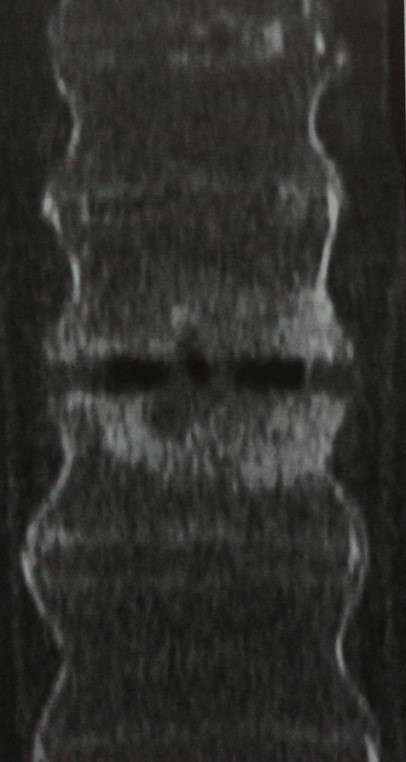

Хроническая травма. Миеломаляция. Сагиттальные Т2- и Т1-зависимые МРТ шейного отдела позвоночника.

При МРТ позвоночника типичными для хронической травмы изменениями спинного мозга являются миеломаляция, киста и атрофия. Посттравматический отёк спинного мозга приводит к его ишемии, с последующим разрушением миелиновой оболочки и развитием глиоза. Кровоизлияние в спинном мозге определяемые на МРТ постепенно рассасывается и формируется киста. Такие кисты часто связаны со спинномозговым каналом, приводя к его расширению – гидромиелии. Внутренние спайки нарушают движение ликвора, приводя к локальным кистам. МРТ СПб позволяет выбирать место выполнения МРТ, мы рекомендуем Вам обследоваться в нейрохирургическом учреждении, где есть опыт диагностики и лечения спинальной травмы.

Локальная киста обычно наблюдается в месте наибольшего сдавления спинного мозга кистой или грыжей диска. Чаще они наблюдаются при травмах шейного отдела позвоночника. При МРТ киста имеет типичный жидкостный сигнал и может быть окружена зоной миеломаляции.

Хроническая травма. Локальная киста. Сагиттальные Т2- и Т1-зависимые МРТ шейного отдела позвоночника.